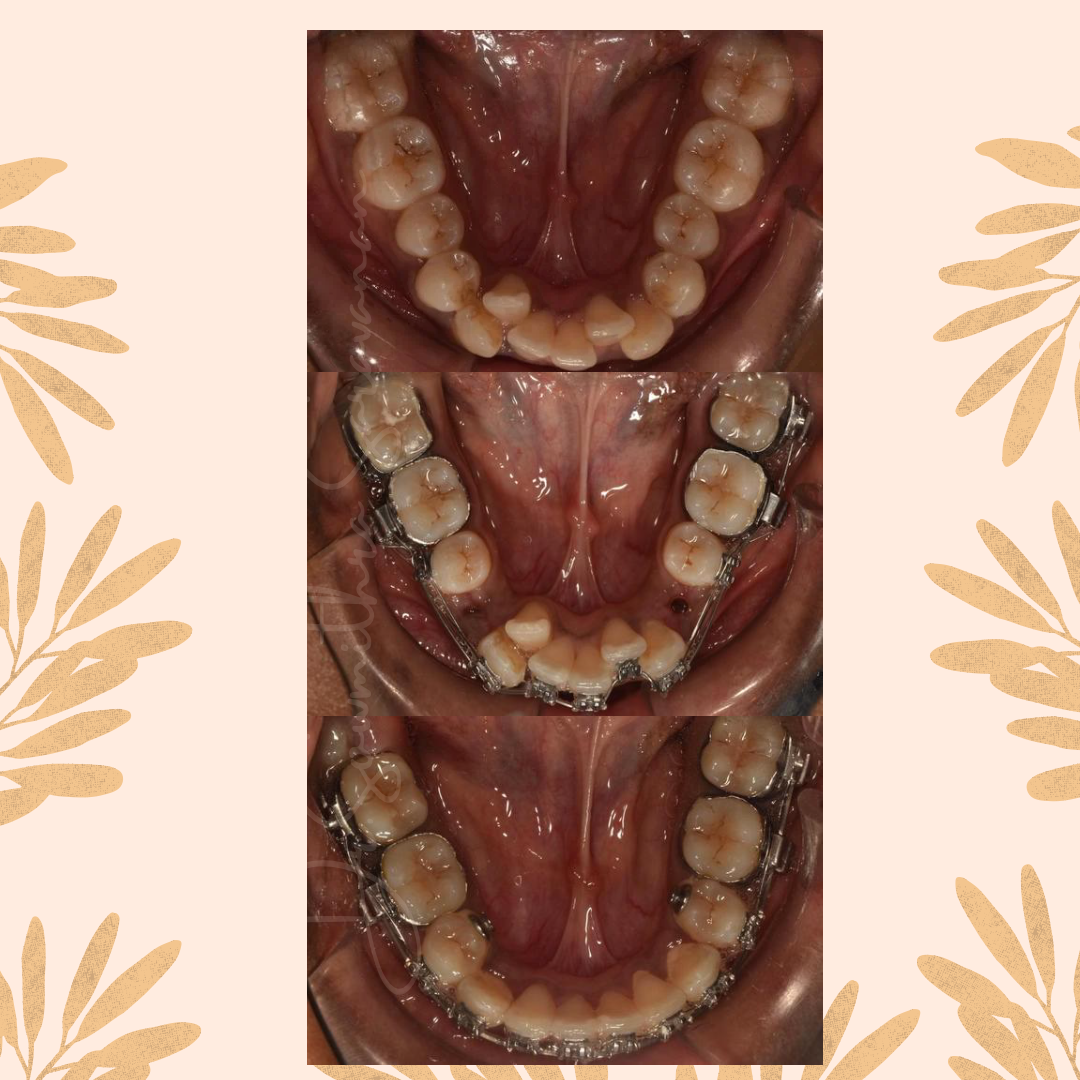

ARCH ALIGNMENT - DECROWDING THE MALPOSED TEETH

ARCH ALIGNMENT - DECROWDING THE MALPOSED TEETH

DECROWDING THE MALPOSED DENTITION

DECROWDING THE MALPOSED DENTITION

ARCH ALIGNMENT - NON-EXTRACTION

ARCH ALIGNMENT - NON-EXTRACTION